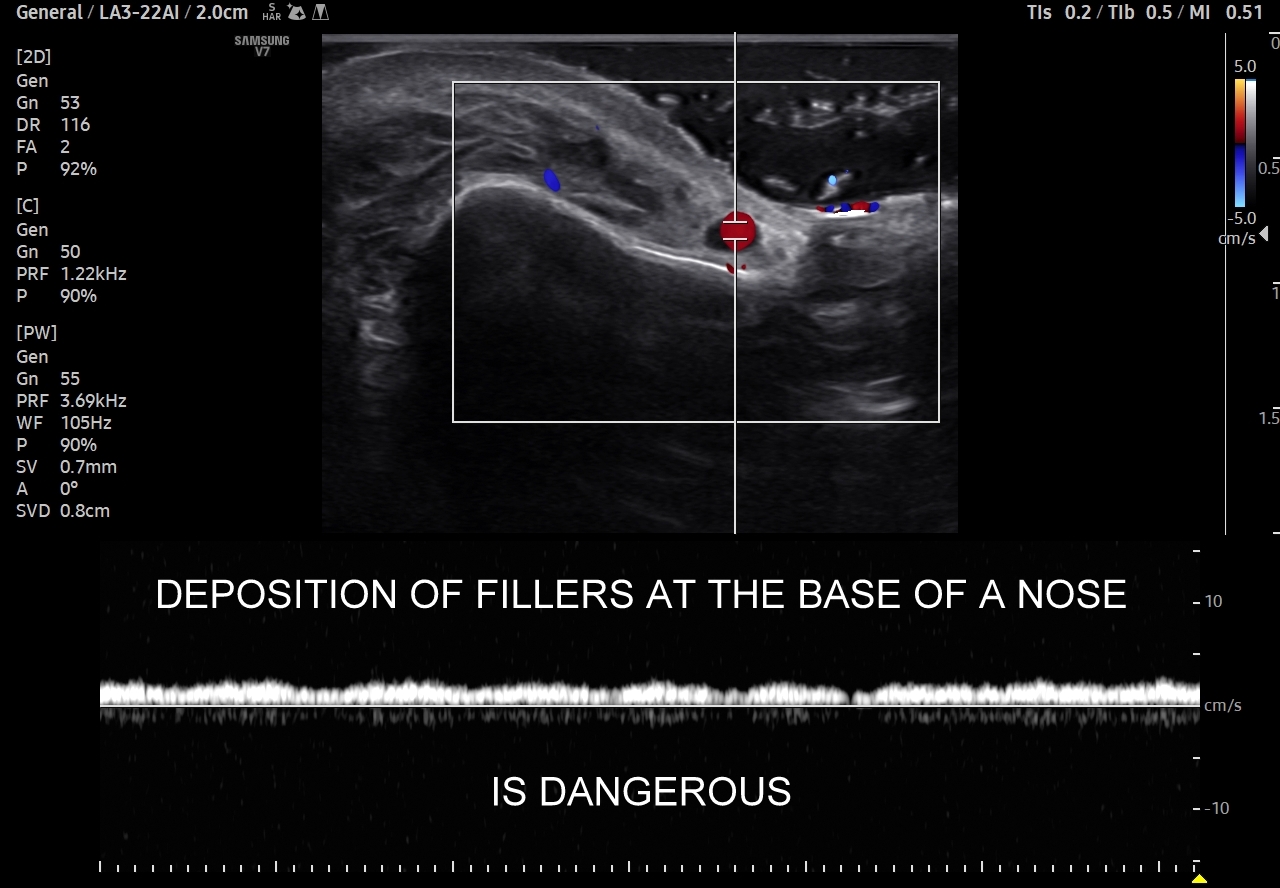

Należy również podkreślić, iż ze względu na gęste upakowanie naczyń, bezpośrednią bliskość anastomoz i często obecność szerokiej, acz niewidocznej żyły kątowej szczególnie niebezpiecznym w aspekcie deponowania wypełniaczy czy wystąpienia lokalnych stanów zapalnych jest obszar u nasady nosa, przy wewnętrznych kącikach oczu i na gładzinie (łac. glabella). Na załączonych do artykułu skanach zobaczyć można czym jest trójkąt śmierci na twarzy i na tej podstawie uzmysłowić sobie, dlaczego tak właśnie się nazywa. Proszę zwrócić uwagę na przykład ekstremalnej bliskości nieodpowiedzialnie zdeponowanego u podstawy nosa wypełniacza, tu kwasu hialuronowego, w stosunku do struktur naczyniowych.